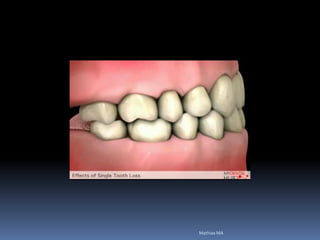

Ausência ou perda dental x implantes

Perdas fisiológicas

Novas dimensões de

rebordos

Atrofias óssea

Redução das dimensões ósseas ideais